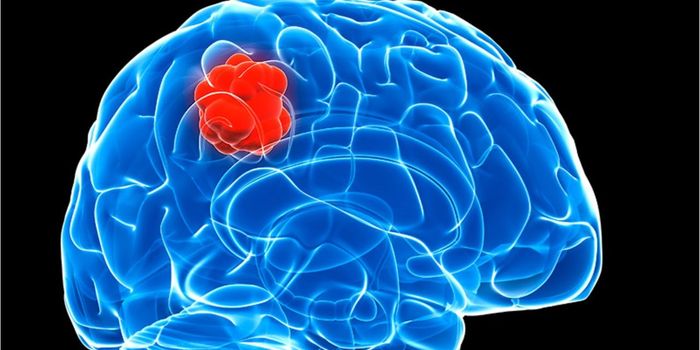

JUL 27, 2017VideosWith the recent news that Senator John McCain is suffering from a brain tumor, there's been a of talk about brain cancer ...

JAN 01, 2018VideosA rare form of brain cancer that strikes mostly children under the age of 10 years old seems centered in a particular ar ...

AUG 31, 2017VideosIn children, brain cancer is the number one cause of cancer-related deaths. Brain tumors are extremely aggressive and of ...